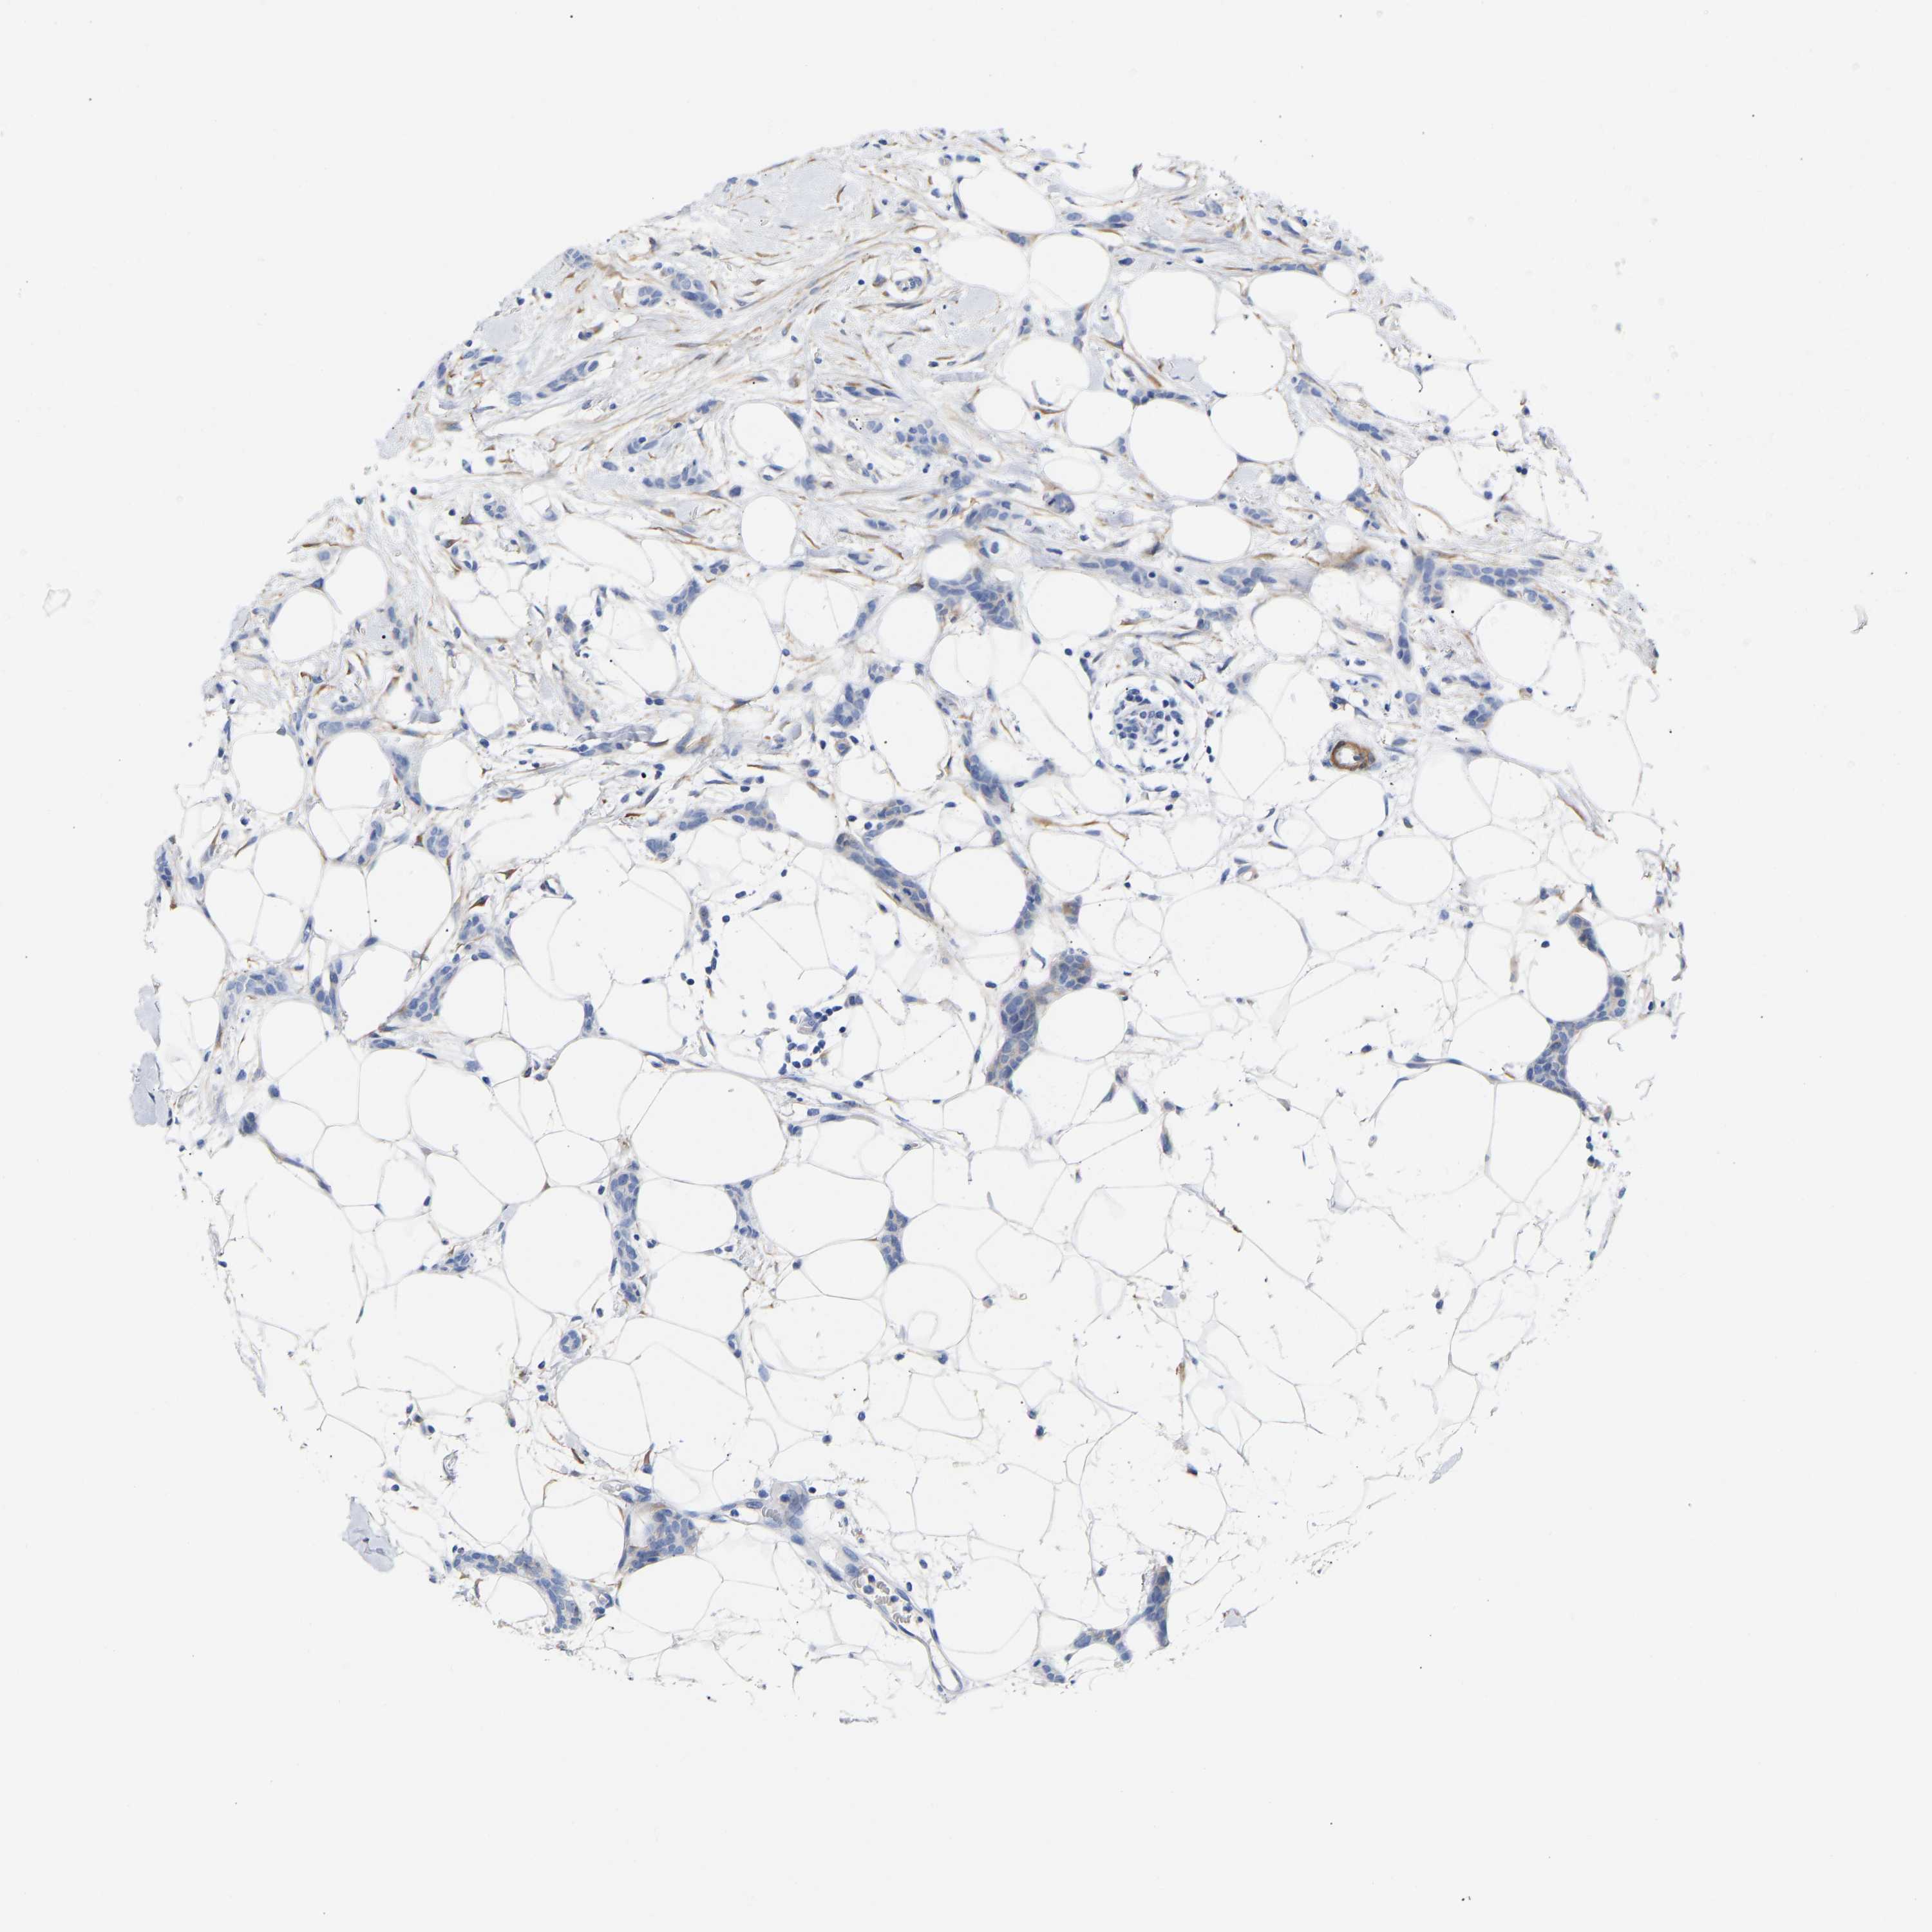

CANCER BREAST CANCER Show tissue menu

BRCA TCGA BRCA VALIDATION PROTEIN EXPRESSION